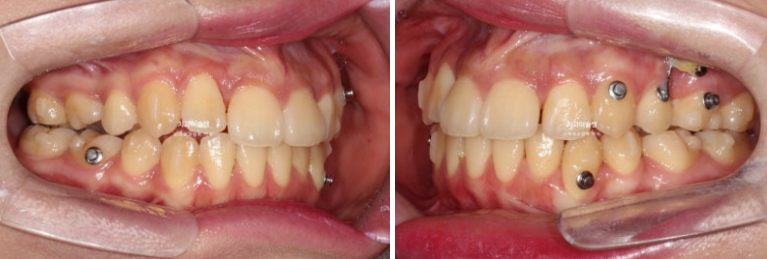

23.10~26.01

개방교합이 해소되어 잘 물립니다

중심선 불일치는 해결이 되었습니다.

교합이 좋습니다.